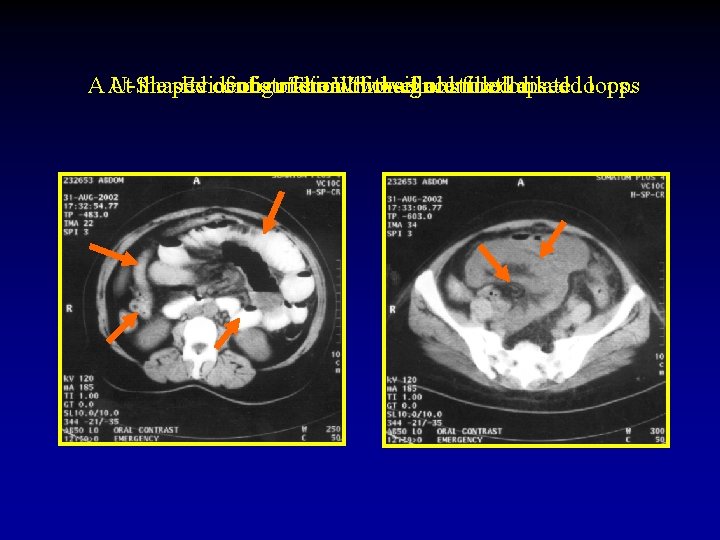

The CT signs of closed loop obstruction of the small intestine are: 1. Evidence of small bowel obstruction. 2. A U-Shaped or radial configuration of the fluid filled dilated loops. 3. At the site of obstruction, a whirl sign, beak sign, triangular loop, or two adjacent collapsed loops.

A At U-Shaped the site Evidence of configuration obstruction of. The small Whirl of two bowel theadjacent sign fluid obstruction. filled collapsed dilatedloops